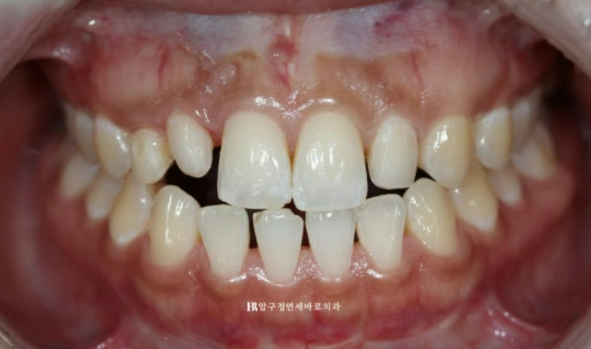

23.02

첫날 측절치의 레진을 제거한 모습입니다. 레진을 제거하고 나니 좌우 남는 공간이나 위치가 많이 다르네요 이 상태에서 무삭제 라미네이트 사이즈가 좌우 같게 제작되기는 어렵습니다.

또 지금처럼 윗니가 아랫니를 덮지 않고 끝과 끝이 일자로 만나는 절단교합 상태에서는 라미네이트 치료 후 깨지거나 떨어지거나 교합 불편감이 생깁니다.

앞니에 절단교합이나 반대교합이 있다면 몇 개월 단기 앞니 교정으로 교합을 좋게 만든 후에나 무삭제 라미네이트가 가능합니다.

이 분도 라미네이트 치료에 앞서 앞니 부분교정을 먼저 하고 하는 김에 아랫니 벌어진 부분 개방교합도 함께 해결하기로 했습니다.